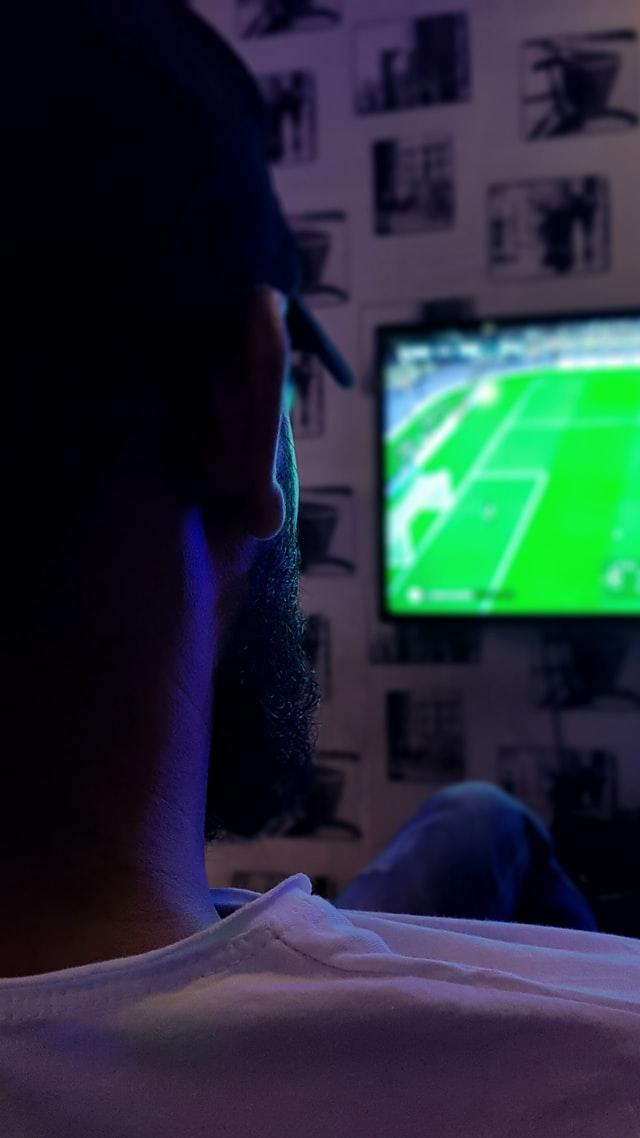

Apyvarpės uždegimas. Kas jį sukelia ir kokį gydymą rinktis?

Apyvarpės uždegimas yra viena iš labai nemalonių lytinių organų ligų, kuri gali…